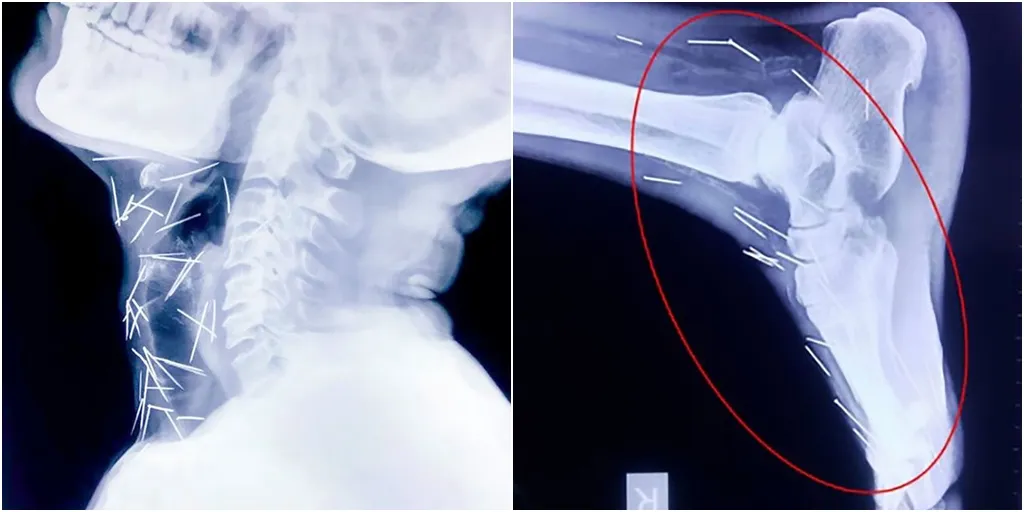

Seorang pria asal India, Badrilal Meena baru-baru ini menggemparkan media karena di dalam tubuhnya terdapat 75 buah jarum. Penemuan jarum dan paku ini mengejutkan dokter yang merawat pria 56 tahun tersebut.

Kondisi ini baru diketahui oleh sang dokter saat Badrilal melakukan operasi rutin pada jempol kakinya. Dokter melihat adanya jarum di tungkai kaki pria asal Rajashtan, India tersebut. Untuk mendiagnosis lebih lanjut, Dokter lalu melakukan x-ray pada Badrilal.

Hasil X-Ray pria ini justru makin mencengangkan. Ditemukan 40 jarum dan paku di tenggorokan Badrilal, 25 paku di tungkai kanan, dan sisanya di kedua tangan. Menurut dokter jarum dan paku ini dimasukkan ke dalam tubuh secara sengaja.